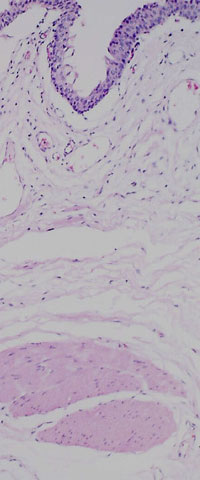

The transitional epithelium of the mucosa appears ragged largely due to post mortem autolytic sloughing of superficial cells.